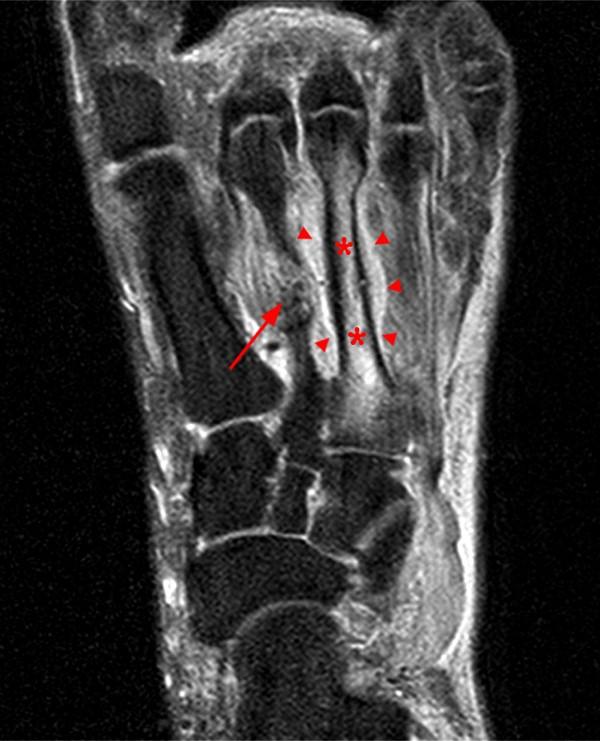

From radsource.us